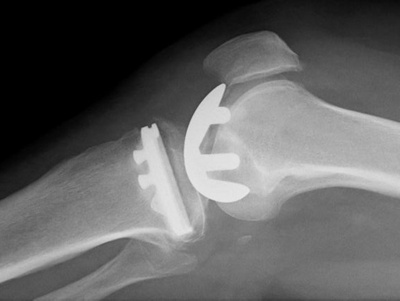

Lorsque seule une partie de l’articulation est usée, c’est-à-dire lorsque l’arthrose ne touche pas fortement toute l’articulation du genou et lorsque l’appareil ligamentaire est encore fonctionnel, il est possible d’opter pour une prothèse partielle de l’articulation. L’opération de prothèse partielle consiste à opérer uniquement la section d’articulation usée en remplaçant la surface osseuse par une surface métallique dans la zone sollicitée au niveau du bas de la jambe et de la cuisse. Cette intervention chirurgicale est beaucoup moins invasive qu’une prothèse totale et permet de conserver le reste de l’articulation du genou avec l’appareil ligamentaire. Pour le patient, cela signifie une réadaptation rapide. Après l’opération, il ressent une sensation plus normale dans l’articulation, et bénéficie d’une meilleure fonctionnalité et d’une meilleure résistance qu’avec une prothèse totale. Cela se ressent en particulier dans les sports dont la pratique exige de plier et de tourner l’articulation du genou.

Une opération de prothèse partielle au niveau de l’articulation du genou est une intervention chirurgicale mini-invasive n’entraînant pas de pertes sanguines importantes. Elle peut se pratiquer sous anesthésie générale ou locale. L’opération doit être parfaitement planifiée de manière à ce que les pièces de prothèse posées puissent former une unité fonctionnelle avec la partie encore fonctionnelle de l’articulation du genou. Une planification minutieuse et l’expérience du chirurgien peuvent permettre de réduire au maximum les risques de complications et d’un résultat défavorable. Comme chaque opération, celle-ci comporte néanmoins des risques, si bien que l’indication d’une opération de prothèse partielle ne peut être posée que lorsque les possibilités de traitement conservateur ne sont plus suffisantes.